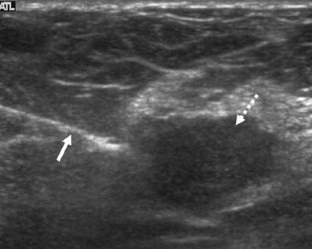

Figure 3